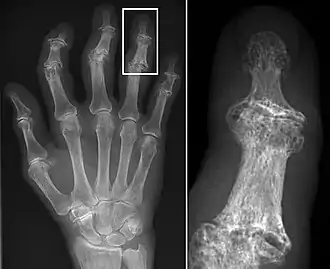

Erosive lesions and marginal lipping associated with hand OA.

Osteoarthritis (OA) is a degenerative joint disease that affects the junctions of articulating elements, or synovial joints (e.g. knee, shoulder) and is characterized by the damage of cartilage. OA is the most commonly documented pathology found in archaeological human remains and has been used extensively as an activity marker that reflects stress-related activity patterns or occupation.[11] Factors such as age, sex, body size and others also affect its expression.[12]

Kathryn Marklein from the Ohio State University explored the prevalence of OA between two Roman period (2nd – 3rd c. CE) skeletal assemblages retrieved from mass graves in Oymaağaç, Vezirköprü, Turkey. It was previously indicated through the analyses of non-metric traits that several individuals from one of the mass graves demonstrated biological relatedness with each other. In order to establish an approach for the evaluation of a possible genetic and socio-historical context correlated with OA, Marklein’s aim was to test if comparing different OA distribution patterns between familial and non-familial groups can indicate familial relatedness at Oymaağaç. Ten synovial joints were selected for the study among adults from site 1 (17 individuals) and site 2 (23 individuals). The study found no significant data to suggest a correlation between OA and different burial group, nor a correlation between OA and biologically related individuals.[13]